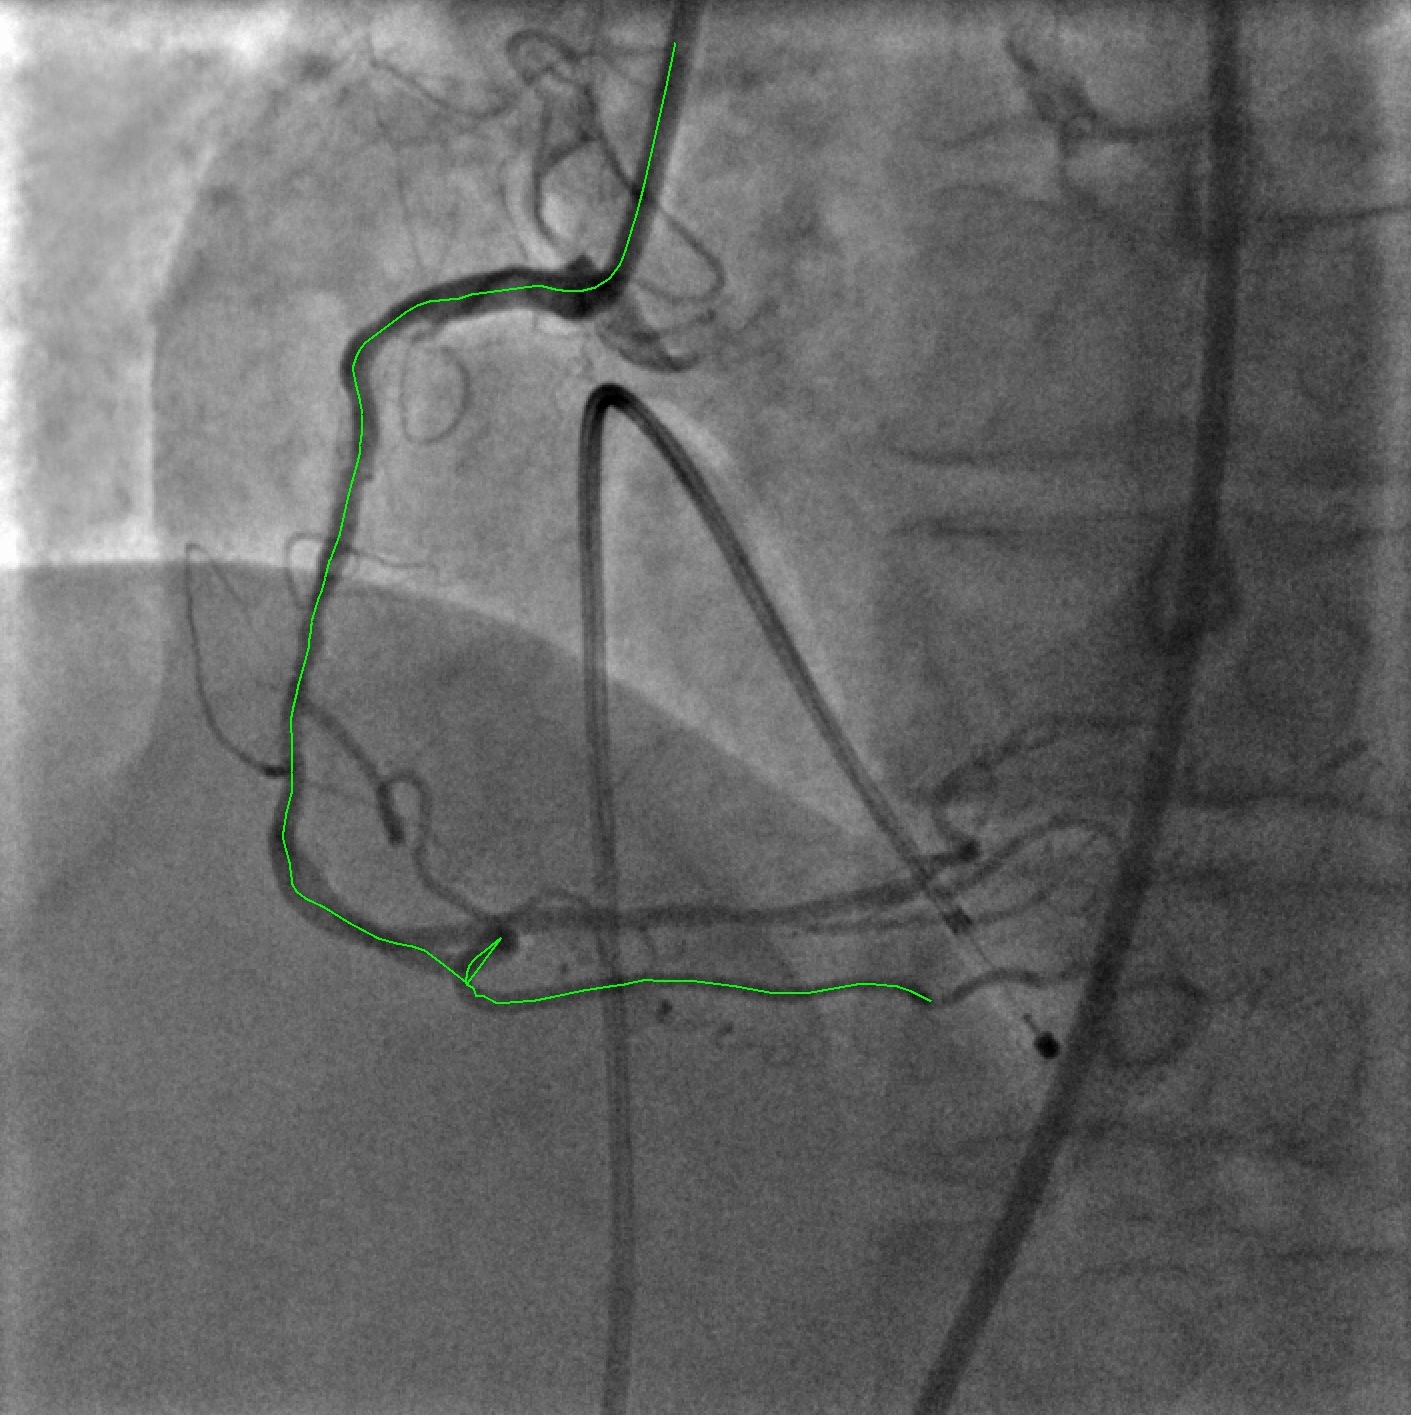

Refer to captionRefer to caption

Figure 2: VOIDD result: ground truth(in green) and vessel of intervention obtained from longest track(in red). In ground truth, the catheter is marked by the expert but not part of the tracked vessel because the guidewire tip is not detected when it is still inside the catheter. In this case, the vessel makes a very tight loop (blue arrow) in the bottom. In the tracking, we fail to detect this loop.

Sequences A1, B1, C1 and D1 in Table 1 show the efficacy of VOIDD algorithm to detect vessel-of-intervention during guidewire navigation in 4 patients and over 1513 images. In summary, VOIDD algorithm is able to correctly determine the location of tip in the vessel-of-intervention with an accuracy of around 88%92%percent88percent9288\%-92\%. The sequences A2, B2, C2 and D2 in the Table 1 portray the efficiency to identify navigation sequence over 690 images when guidewire tip is absent in the fluoroscopic images. The VOIDD algorithm is able to detect these sequences as sequence without guidewire tip with accuracy of 98%99%percent98percent9998\%-99\%. Analyzing the navigation sequence detection accuracy of VOIDD, we can use it to automatically detect the arrival of the guidewire tip. The parameters involved in various stages of the algorithme.g. tip candidate extraction or TAD were designed based on the physical properties of guidewire tip, permissible speed of advancement of guidewire. Current implementation runs in average 0.330.330.33 seconds for tracking on a Intel Core i7 cadenced at 2.802.802.80 GHz. Videos are available as supplementary material111https://voidd-miccai17.github.io/. Figure 2 shows the vessel of intervention obtained by the VOIDD algorithm and corresponding ground truth on left.